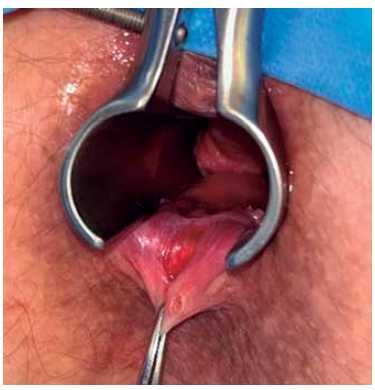

Paciente de 35 anos com queixa dor intensa na região do períneo, antecedente de obesidade e diabetes mellitus não insulinodependente. Apresenta exame físico ilustrado pela imagem a seguir.

Enunciado 4449354-1

(Arquivo pessoal; imagem utilizada com autorização)

Na triagem, foram observadas febre e taquicardia. Realizados exames laboratoriais de urgência, que identificaram leucocitose e aumento de provas inflamatórias.

A respeito do quadro apresentado, assinale a alternativa correta.